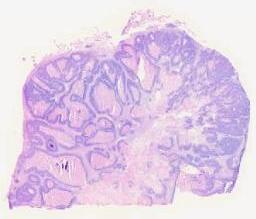

临床资料: 女39岁,九个月前自行触及肿块,无乳房疼痛、乳头溢液、瘙痒、皮肤红肿、发热、乏力等,乳腺超声示:右侧结节位于2-3点方向,大小约3.2*3.2*1.9cm,周边可见血流信号。BI-RADS4b类。家族史:母亲乳腺癌

临床资料: 女,43岁,胃癌术后5年,发现盆腔包块1年余。患者5+年前因“胃癌”行胃大部分切除术+术后规范化疗8次。术后每年定期体检。1年余前阴道彩超提示盆腔包块,大小约4*3cm,未重视未就诊。后完善盆腔MRI检查提示:右侧卵巢囊性病变,考虑:炎性包块可能,伴出血,输卵管积水,上皮来源肿瘤及转移瘤待排。辅助检查:盆腔MRI示:1.右侧卵巢囊性病变,考虑:炎性包块可能,伴出血,输卵管积水,上皮来源肿瘤及转移瘤待排,请结合临床。2.左侧附件及子宫颈多发囊性灶。经腹部+阴道联合扫查:子宫呈前位,切面大小、形态正常,包膜光滑,肌壁回声均匀;宫腔线居中,内膜厚约15.6mm,回声不均匀。右侧附件区可见一囊实混合性包块,大小约71×52mm,边界尚清,形态不规则,CDFI:包块周边可见少许点状血流信号。左侧附件区未见明显包块回声。子宫直肠窝未见明显游离无回声区。